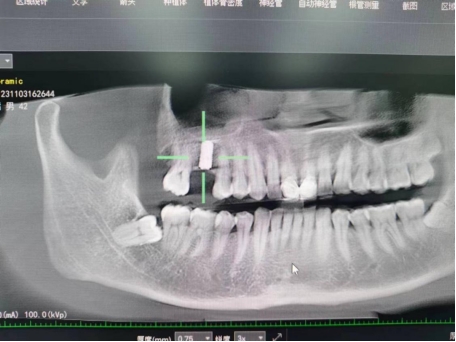

武先生术后检查图

武先生术前检查图

据了解,53岁的武先生,因右上后牙缺失多年,缺失的牙齿给他造成了不小的烦恼,影响到了正常咀嚼功能。在了解到小艾电竞 口腔科能开展种植牙手术以后,武先生前来咨询,经过仔细全面的口腔检查和CT检查、检验等检查,武先生符合种植牙条件,决定实施右上后牙区种植牙的修复方案。本次手术由陈河林博士主刀,黄魁副主任做助手,在口腔中心成功完成该院首例种植牙手术,手术历时约30分钟,术中微创操作,患者全程无痛,术后无不良反应,整个诊疗过程舒适、安全、精准,经术后CT检查种植体位置精确。